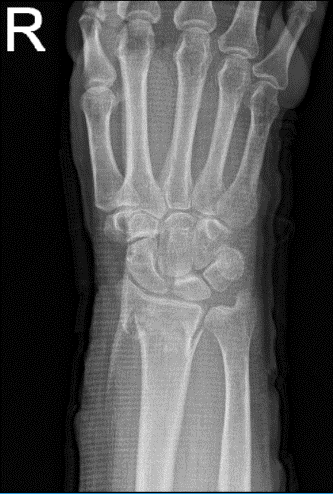

The patient presented an MRI result which contained Colles’ fracture with dorsal angulation.

Right wrist X-ray 3 or more views